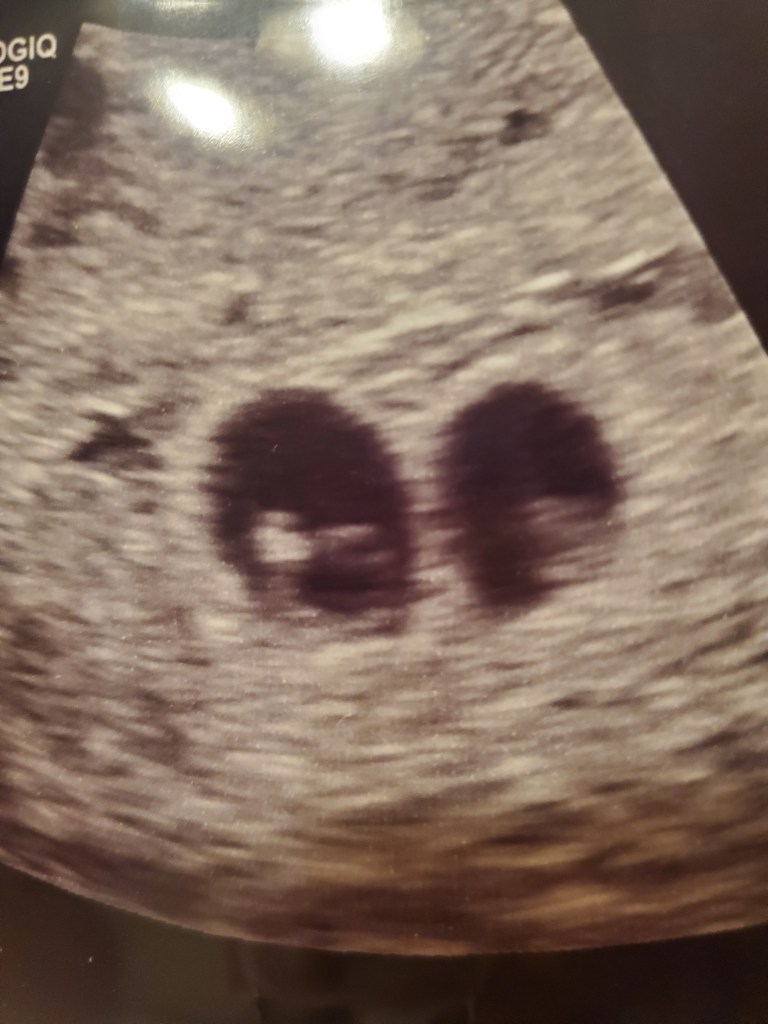

I went yesterday for my anatomy scan of both babies and got great news that everything is looking perfect and healthy and we are expecting two baby girls, Harper and Hadley!

The ultrasounds are more frequent with twin pregnancy and I am absolutely loving it! The ultrasound techs have been very generous with pictures too!

At 20 weeks they don’t have alot of chunk to them just yet. They are 10 ounces each and will be packing on the pounds soon! I can’t wait to share more of our journey with our twins.